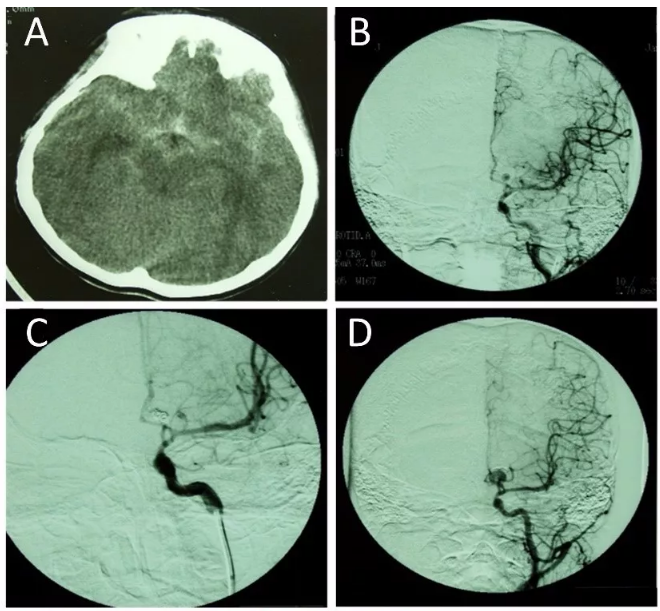

图一:如图是一个12岁的男性破裂动脉瘤患者。破裂动脉瘤位于左侧前交通动脉A1段(A-B);经介入治疗后,可见动脉瘤完全闭塞(C);但术后3个月的随访DSA显示该动脉瘤复发(D);在术中可见动脉瘤内的填充物(E);将动脉瘤及填充物移除后,成功夹闭动脉瘤(F-G);术后复查DSA显示动脉瘤完全闭塞,未见复发(H)。